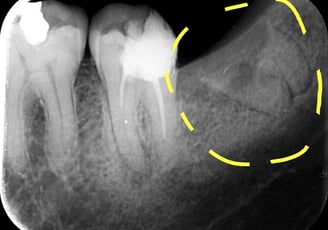

Radiografii retroalveolare

Aceste radiografii sunt utilizate pentru a evalua structurile osoase ale maxilarelor și mandibulei, fiind utile în special pentru tratamente ortodontice sau implanturi dentare.